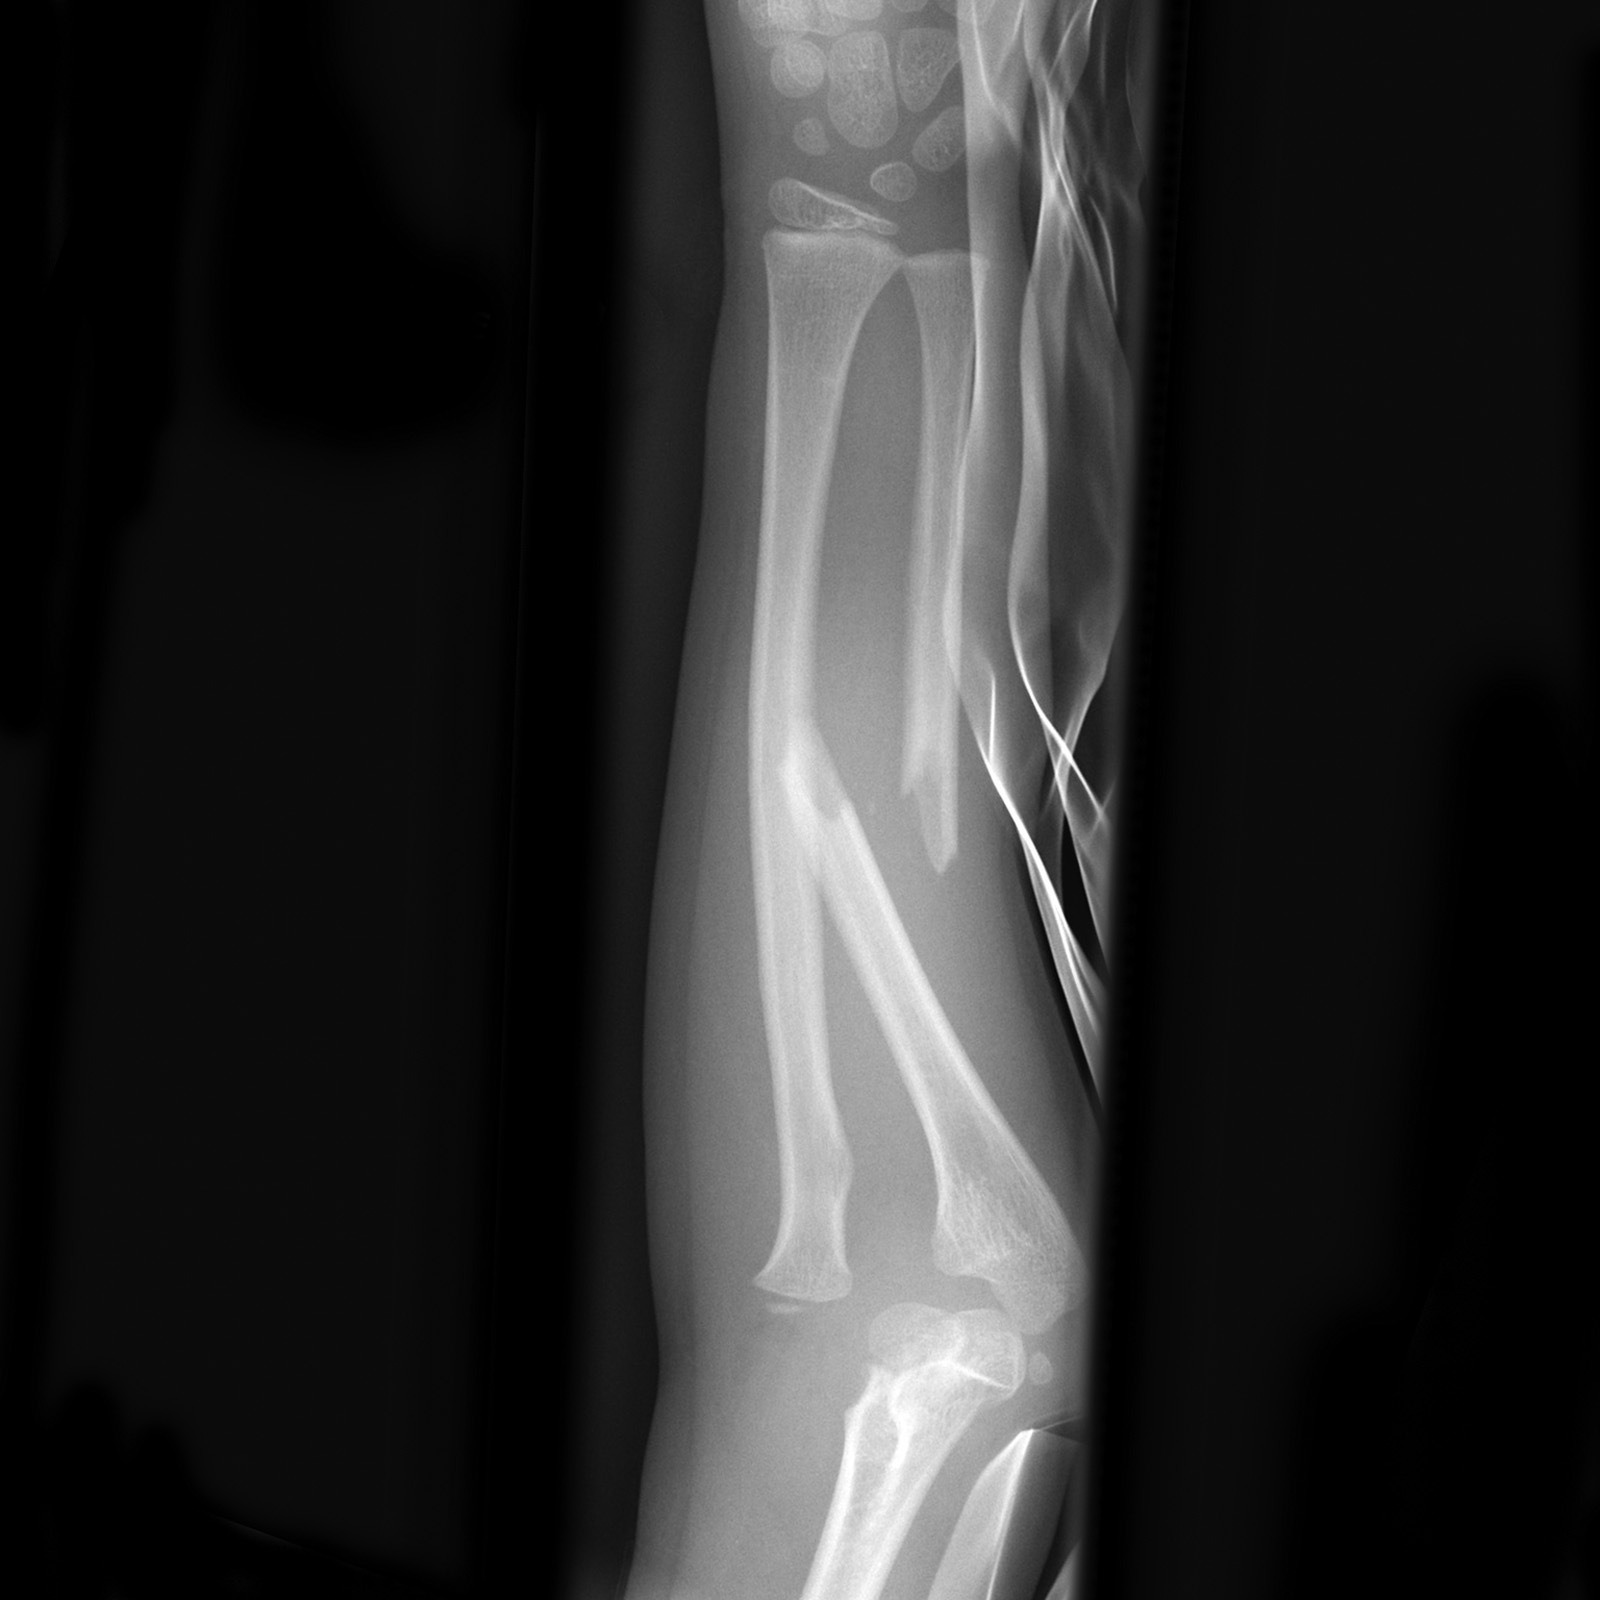

Beschreiben Sie die Befunde auf dem vorliegenden Röntgen des Unterarms und nennen Sie die Diagnose. Kenne Sie eine ähnliches Verletzungsmuster, welches jedoch den distalen Unterarm betrifft?